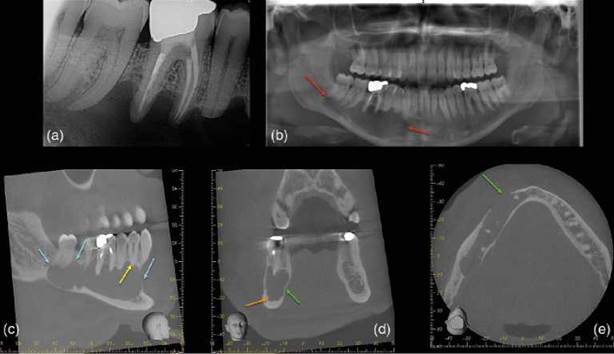

Radicular cyst. This is the most commonly found cyst in the jaw and usually originates from the epithelial cell rests of Malassez. These cysts most commonly occur in patients between 30 and 50 years old [122], and are associated with non-vital or root treated teeth, the most commonly affected tooth is the maxillary lateral incisor. It is uni- formly radiolucent, round, unilocular, with smooth, well defined and corticated margins [123]. There may be cortical plate expansion, and displacement of adjacent teeth (Figure 6.19).

Odontogenic keratocystic tumor. This is a unilocular or multilocular, benign tumor, which emanates from the dental lamina epi- thelium and is most commonly detected in the posterior body and/or angle of the man- dible or maxillary canine regions. It has well- demarcated b orders, is uniformly radiolucent, and can expand considerably within the can- cellous bone (Figure 6.20).

Figure 6.19 Radicular cyst. (a, b) Parallax periapical radiographs reveal a well-defined periapical radiolucency associated with the root treated lower right first molar tooth (green arrow). (c) Sagittal reconstructed CBCT scan reveals a well-defined periapical radiolucency extending from the lower right second premolar to the lower right second molar teeth which has resulted in apical resorption of the root apices. (d) coronal and (e) axial reconstructed CBCT slices reveal marked buccal expansion and perforation of the buccal cortical plate (red arrow). The inferior dental canal (yellow arrow) has been deflected inferiorly.

Figure 6.20 Odontogenic keratocyst. (a) Periapical radiograph reveals a large radiolucency associated with the lower right premolar and root treated molar teeth. (b) Dental panoramic tomograph reveals the extent of the lesion (red arrows). (c-e) Sagittal, coronal and axial reconstructed CBCT slices reveal a large well-defined pseudo-loculated radiolucency in the body of the right mandible extending from lower right incisor to the retromolar, which rises up between the roots. There are signs of external inflammatory resorption associated with the lower right premolar teeth, but not with the root-canal-treated lower right first molar tooth, indicating that the lesion is not inflammatory. The lesion has resulted in thinning out and buccal expansion of the cortices (green arrow), and is in close proximity to the inferior dental nerve (orange arrow).

Nasopalatine (incisive) canal cyst. These cysts affects 1% of the population, typically males between 40 and 60 years old. It presents as a round or oval radiolucency with smooth and well-demarcated borders in the midline immediately posterior to the maxillary central incisor teeth [123].

It is uniformly radiolucent, and may cause the adjacent teeth to be displaced as it expands (Figure 6.21). The adjacent teeth normally respond positively to vitality testing, thus aiding differential diagnosis.

Figure 6.21 Naso-palatine canal cyst. (a, b) Periapical radiographs reveal attempted accessed cavity in the upper right central incisor. There is a large, well-defined and partially corticated radiolucency spanning UL1, UR1, UR2 and UR3. The lesion is displacing the UR1 (yellow arrow), and there is no evidence of root resorption. (c) Axial and (d) coronal CBCT reconstructed slices reveal lobulated, radiolucent radiolucency with minimal expansion of the cortical plates (red arrows), (e) sagittal view reveal that the radiolucency appears to be merging with the incisive foramen (blue arrow).